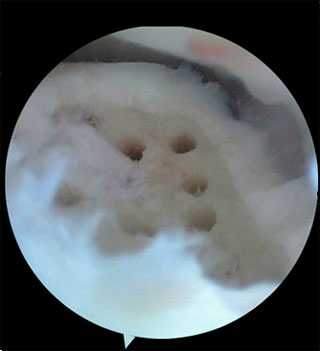

3 этап: удаление дефекта суставной поверхности таранной кости и замещение его трансплантатом:

- С помощью костной ложки или скальпеля определите точные границы стабильного хряща

- Удалите дефект фрезой подходящего размера и измерьте глубину получившегося ложа (рис. 16)

Нюансы 3 этапа операции:

• В зависимости от дефекта используйте фрезы диаметром 4,5, 6,5 или 10 мм

• Рассверлите основание ложа для стимуляции заживления за счет естественного кровотока окружающей костной ткани

- дебридмент и стимуляция костного мозга (микрофрактуринг, абразивная хондропластика, перфорация); При этом за счет выхода стволовых клеток из костно-мозгового канала в область дефекта нарастает новый суставной хрящ.

Методика заключается в удалении всех отколовшихся фрагментов хряща и подлежащей некротизированной (умершей) кости. Если в кости под хрящом имеются кисты, они вскрываются и специальным образом обрабатываются. Затем особым интструментом выполняется микро перфорация кости. Это приводит к высвобождению факторов роста, которые заполняют дефект хряща таранной кости.

Происходит стимуляция образования новых сосудов, в остеохондральный дефект выходят стволовые клетки костного мозга таранной кости, и он в последующем заполняется хрящом.